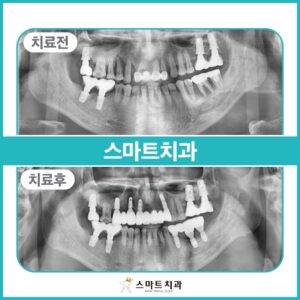

반여동치과 오래된 보철물에서 냄새가 난다면

안녕하세요. 반여동치과 스마트치과입니다. 입에서 알 수 없는 구취가 계속해서 난다면 오래된 보철물이나 치주질환, 소화기 문제 등을 생각할 수 있는데요. 몸에 이상이 없고 잇몸이 튼튼하다면 오래된 보철물을 의심해볼 수 있습니다. 보철물의 수명 기간은 보통 10년 이내이며, 이상이 없더라도 주기적으로 검진하며 확인해보는 것이 좋은데요. 오늘은 오래된 보철물로 인해 본 원에 내원해주신 환자분을 더보기…